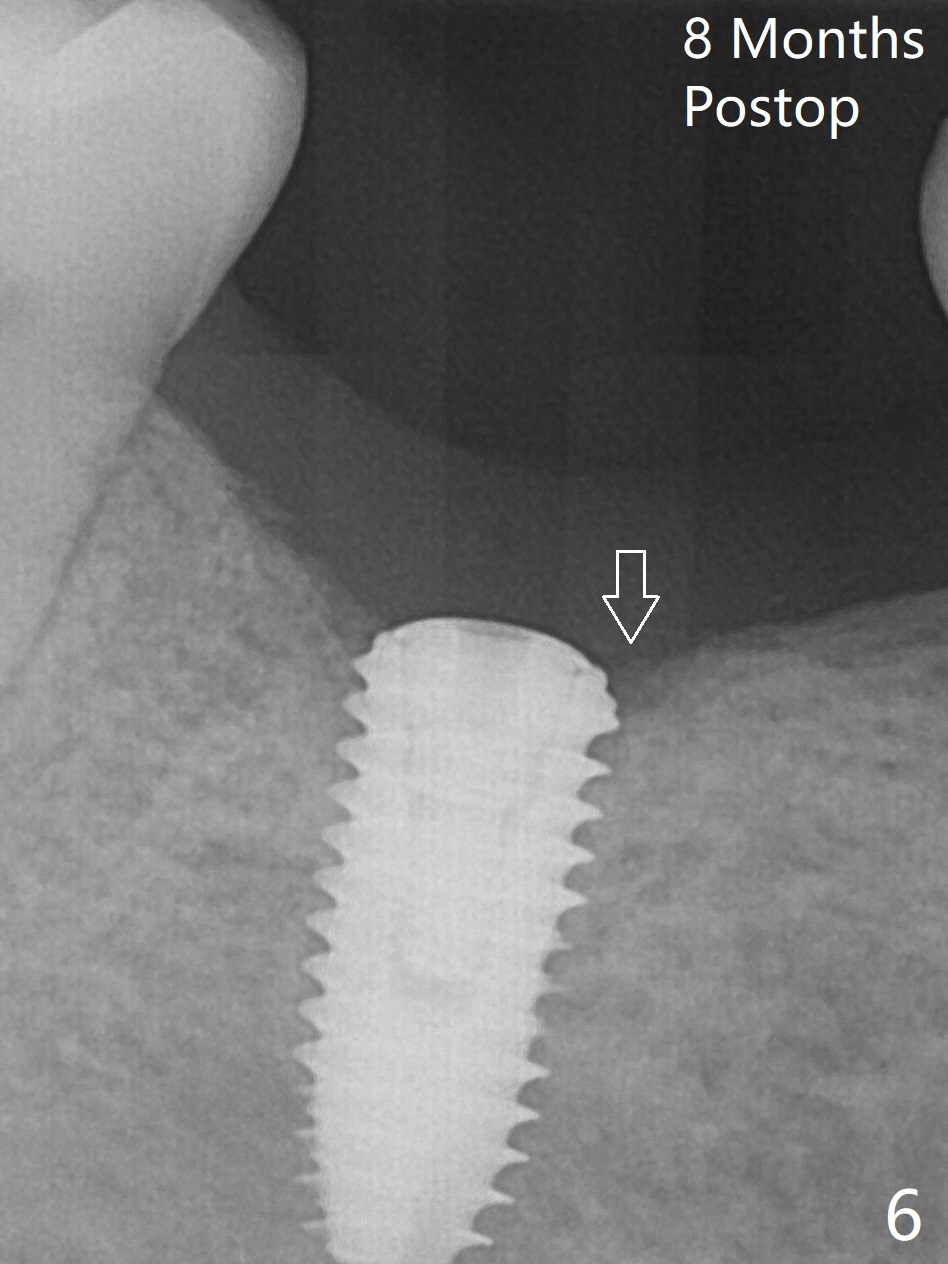

Because of severe pain, block anesthesia is administered prior to extraction. The mesial socket of the tooth #30 is deep with granulation tissue. A 4.5x10 mm dummy implant is placed with < 40 Ncm following sequential osteotomy until 4x13 mm over the septum (Fig.1 (low density)). After 4.5x13 mm drill, a 5x10 mm dummy implant is inserted with <40 Ncm (Fig.2). Since the Inferior Alveolar Canal is invisible (Fig.1,2 (pan should have been taken)), a 5x11.5 mm implant is placed with <20 Ncm. When a 6.5x5.5(3) mm abutment is placed, the underlying implant is turned (Fig.3). With collagen plug is placed in the distal socket and Vera graft around the implant, an immediate provisional is fabricated and relined. When it is seated, it has mobility. In fact the provisional should be locked into the edentulous area while it is malleable. To prevent low primary stability, osteotomy should be under prep, since the implant (red circle) contacts only two bony surfaces, i.e., the mesial (M) and distal (D) walls of the mesial socket (Fig.4 (occlusal view) black oval). There are gaps buccally (B) and lingually (L). In case of low stability, a healing screw or abutment should be placed; the remaining socket is closed with suture. The provisional is loose 19 days postop; it is removed by sectioning. A healing screw is placed. Twelve days later, the wound heals (Fig.5). The patient returns for uncover 8 months postop; although the implant has osteointegrated apparently, the crestal bone resorbs to the implant plateau level (Fig.6 arrow). It seems that the immediate implant should be routinely placed 2-3 mm deeper. The open margin is closed with composite when the abutment/crown is removed after cementation (Fig.7).